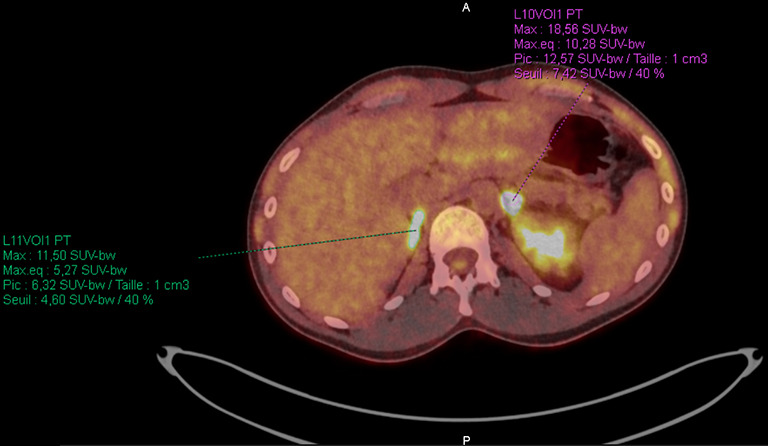

背景:IV期非小细胞肺癌不是一个可治愈的阶段。然而,一种局部治疗原发肿瘤的新方法可能会提高无进展生存期。放疗或手术的选择,以及这些治疗的最佳时机仍有待确定。我们在这里报告第一例,据我们所知,一个多转移患者在新辅助阿勒替尼治疗后接受巩固手术,导致完全的病理反应。病例描述:该患者是典型的致癌改变人群,如间变性淋巴瘤激酶(ALK)重排,年轻,不吸烟;然而,他是男性。支气管内窥镜检查证实支气管肺腺癌,免疫组化显示ALK强表达。我们启动了alectinib作为转移性疾病的一线治疗;然而,由于诱导的低转移性疾病,在多学科委员会上讨论了原发肿瘤的局部治疗。行肺叶切除术,组织学检查证实完全病理反应。由于缺乏可用数据,佐剂alectinib持续时间未确定。结论:该病例提示,局部治疗,即使是IV期患者,在对全身治疗有最佳反应的时候进行,可能会改善无进展生存期,甚至可能是治愈的一瞥。

Case description: The patient was, as is typically observed in populations with oncogenic alterations such as anaplastic lymphoma kinase (ALK) rearrangements, a young and non-smoker; however, he was male. Bronchial endoscopy confirmed the diagnosis of bronchopulmonary adenocarcinoma with strong ALK expression demonstrated by immunohistochemistry. We initiated alectinib as first-line treatment for metastatic disease; however, due to the induced oligo-metastatic disease, a local treatment of the primary tumor was discussed during multidisciplinary board. Lobectomy was performed and histological examination confirmed the complete pathological response. Adjuvant alectinib was continued for unspecified duration due to the lack of available data.